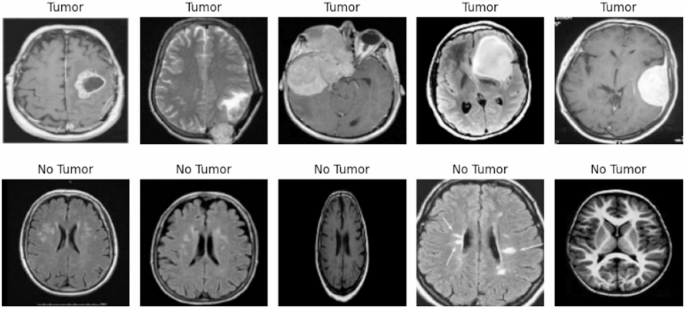

Sample Images from Dataset (Tumour and No Tumour)36.

Figure 4 shows images from the dataset, categorized into “Tumour” and “No Tumour” classes. These images involve image resizing, where all images are standardized to a uniform dimension of pixels. This ensures that the images are compatible with the deep learning model and reduces computational complexity.